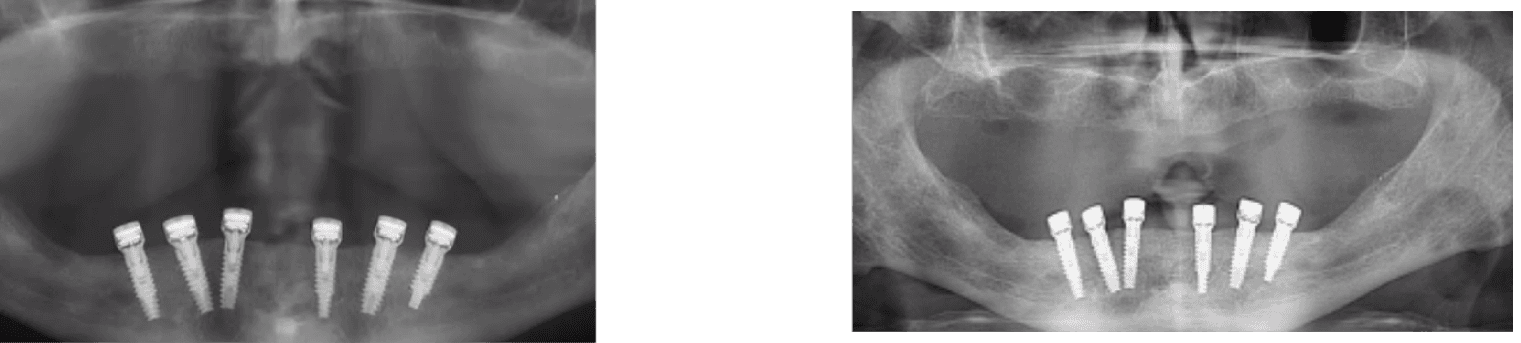

A 70-year-old healthy patient presented with inflammatory environment and advanced vertical bone loss around two adjacent implants supporting a fixed bridge. The treatment protocol included removal of the prosthetic bridge, thorough non-surgical debridement and deep curettage of the affected sites, followed by the application of MED healing abutments to promote bone regeneration and reduce inflammation through localized electromagnetic stimulation.

Within three months, radiographic evaluation revealed substantial vertical bone regeneration, effectively restoring nearly the entire height of the previously resorbed bone. Bone levels improved from 2.5 mm and 2.3 mm of loss at baseline to 1.2 mm and 2.0 mm of residual pockets, representing approximately 100% recovery of the lost bone height. The regenerated bone exhibited dense, well-integrated structure, and the peri-implant tissue remained healthy with no recurrent inflammation.

• This case demonstrates the regenerative capability of MED healing abutments in reversing peri-implant bone loss and achieving implant preservation through a predictable, minimally invasive, and non-surgical approach.